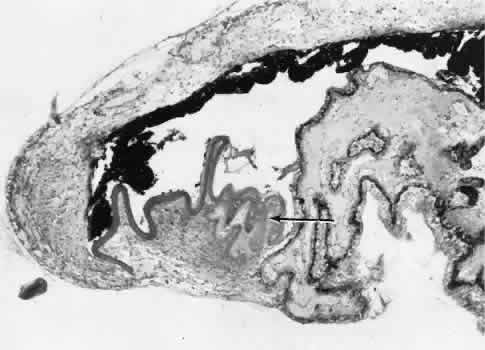

Fig. 20. Cyclodiathermy treatment of the ciliary body to control glaucoma. A. Gross photograph illustrates extensive areas of depigmentation mainly in the region of the pars plana (arrows) rather than the pars plicata. B. Light micrograph of the region of the pars plana illustrates an extensive area of tissue degeneration of the pars plana (between arrows) in the late postoperative course. C. Light micrograph of the destructive effects of cyclocryotherapy also in the region of the pars plana and pars plicata. The ciliary epithelium in the early postoperative period is necrotic and cystic. (Hematoxin-eosin stain; A, × 8; B, × 16.)